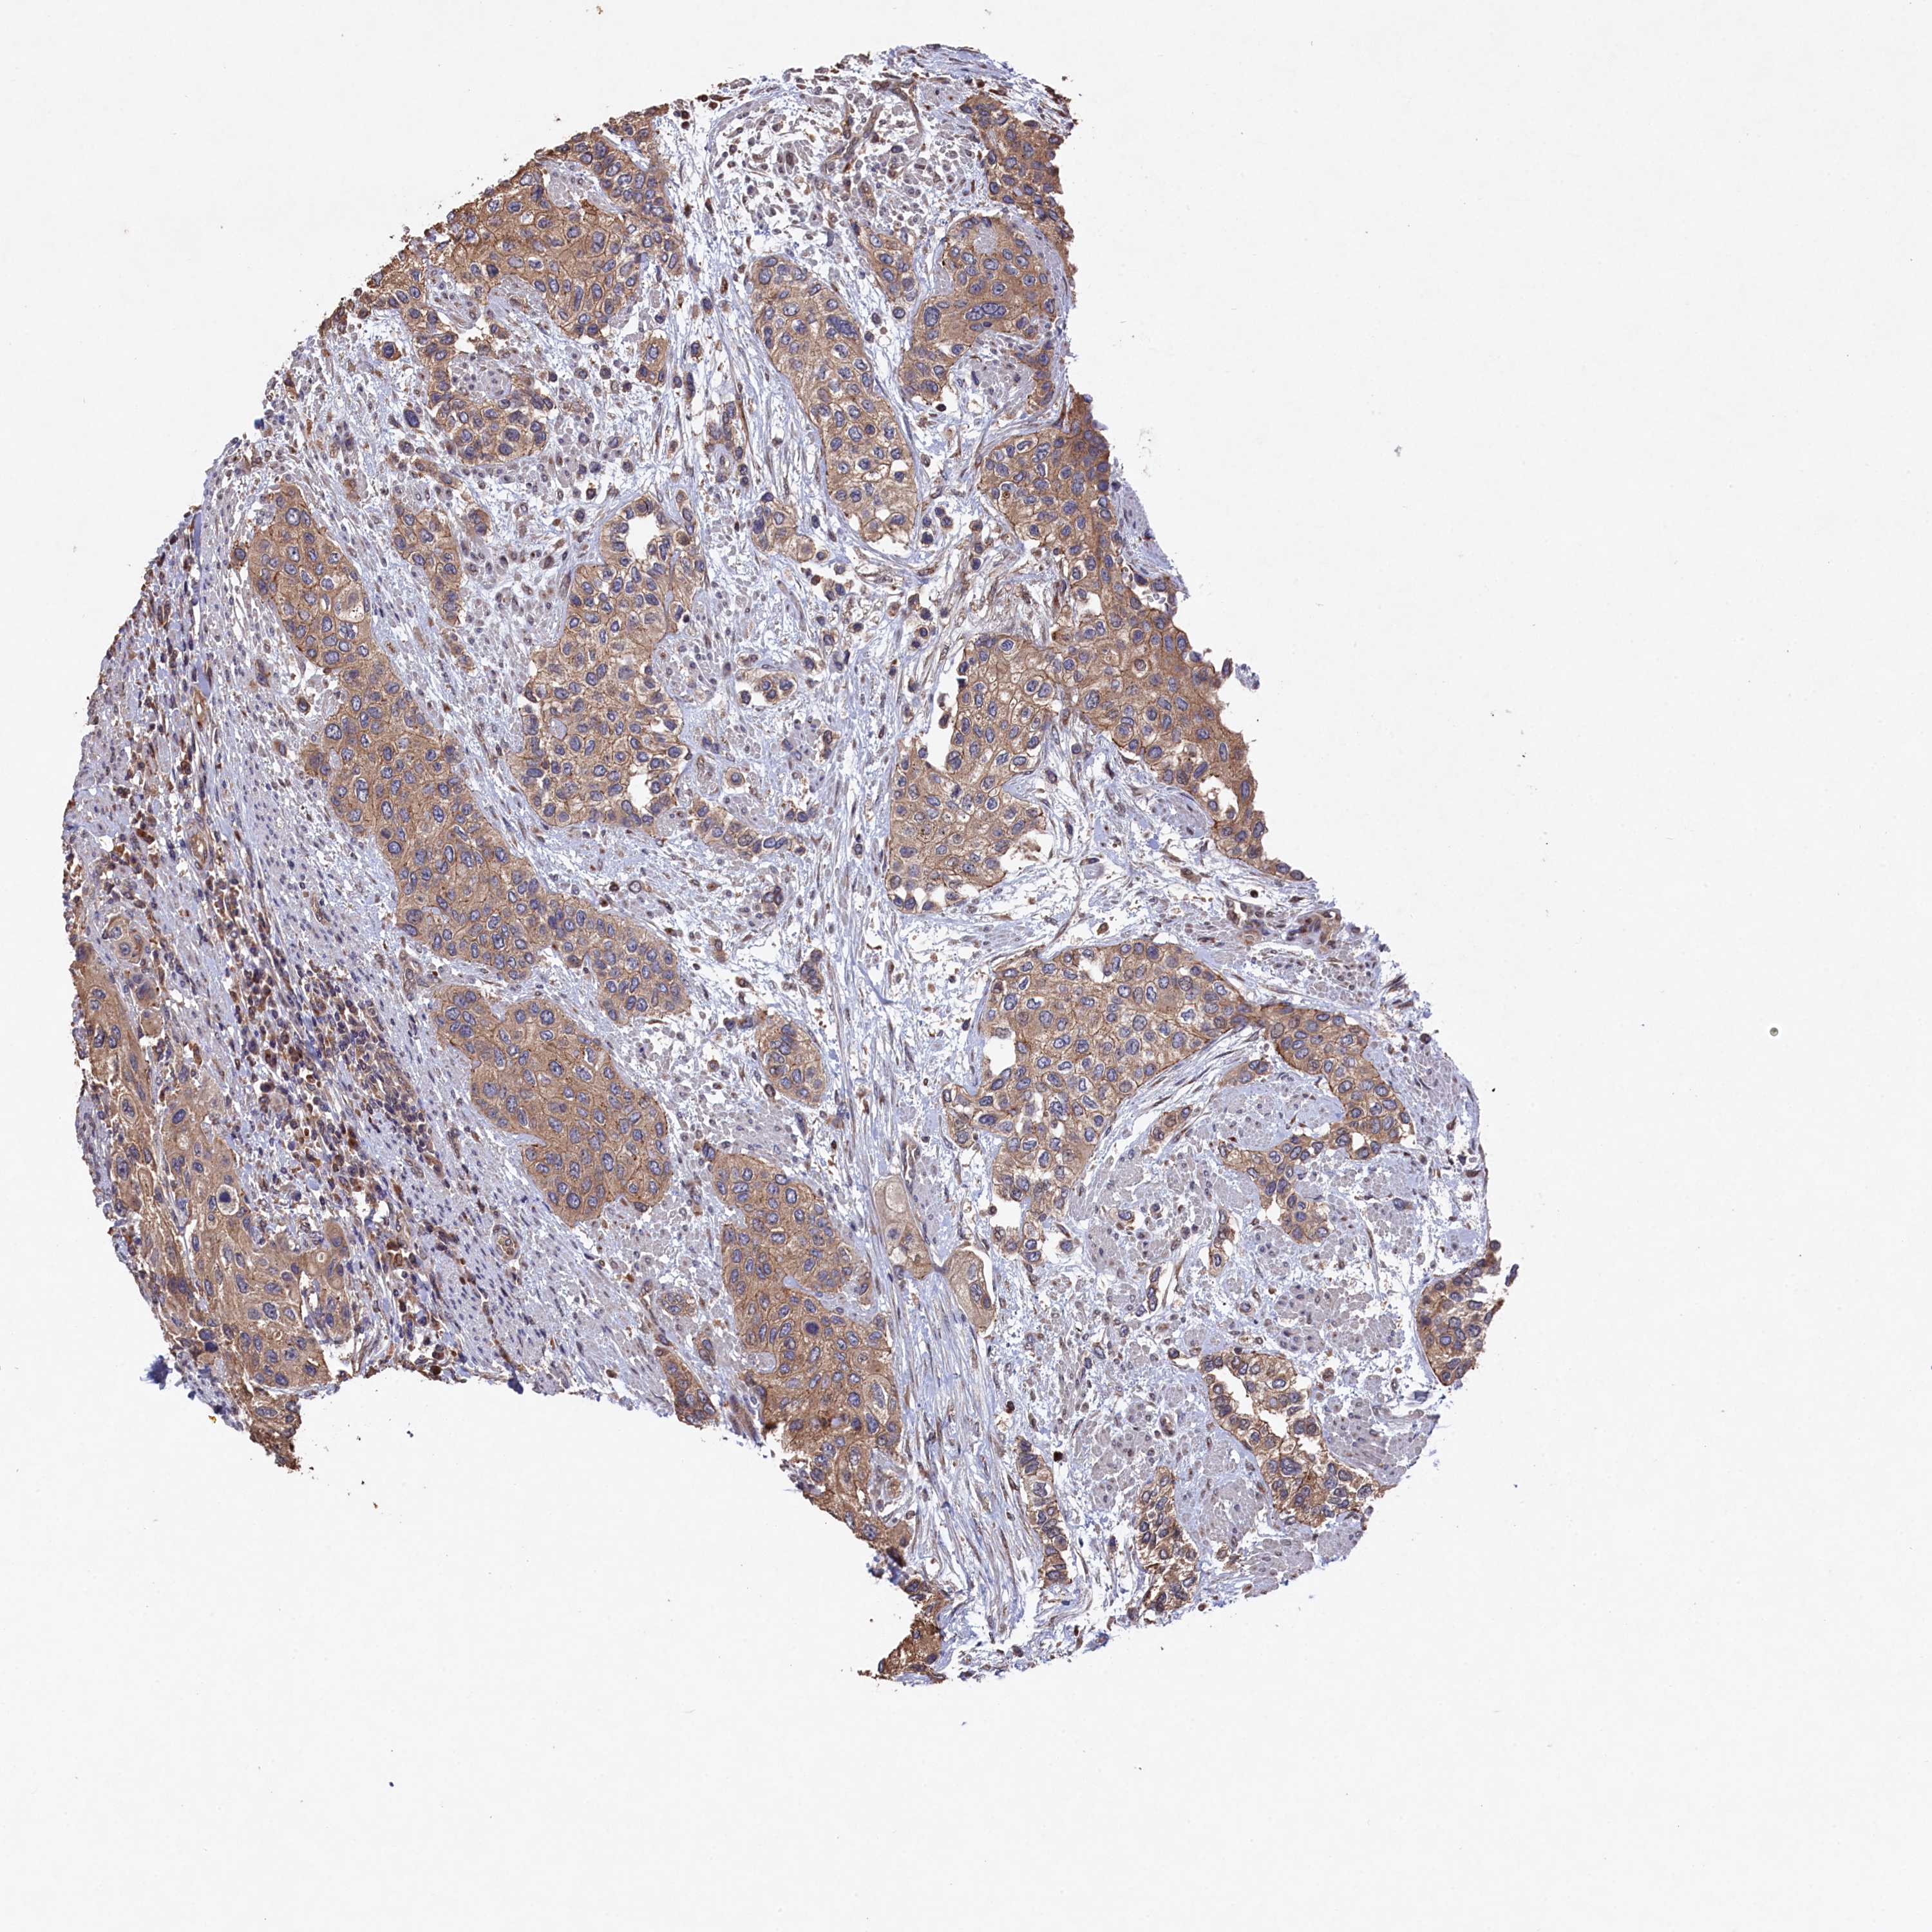

UROTHELIAL CANCER - Protein expressioni

A mouse-over function shows sample information and annotation data. Click on an image to view it in a full screen mode. Samples can be filtered based on level of antibody staining by selecting one or several of the following categories: high, medium, low and not detected. The assay and annotation is described here.

Note that samples used for immunohistochemistry by the Human Protein Atlas do not correspond to samples in the TCGA dataset.

Antibody stainingi

Antibody staining in the annotated cell types in the current human tissue is reported as not detected, low, medium, or high, based on conventional immunohistochemistry profiling in selected tissues. This score is based on the combination of the staining intensity and fraction of stained cells.

Each image is clickable and will lead to virtual microscopy that enables deeper exploration of all samples and also displays staining intensity scores, fraction scores and subcellular localization as well as patient and tissue information for each sample.

Antibody HPA040916

Staining

High

Medium

Low

Not detected

Intensity

Strong

Moderate

Weak

Negative

Quantity

>75%

75%-25%

<25%

None

Location

Nuclear

Cytoplasmic/membranous

Cytoplasmic/membranous,nuclear

Urothelial carcinoma, Low grade